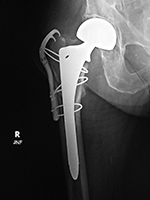

| Bipolar hemiarthroplasty with claw plate and cables

Bipolar hip prosthesis with cable plate (cables passed through the plate) |

| 78 year-old woman with prior bipolar hemiarthroplasty; presently treated with claw plate and cables for intertrochanteric fracture.

The cable plate and wires stabilize a periprosthetic femoral shaft fracture. From Taljanovic, 2005 |